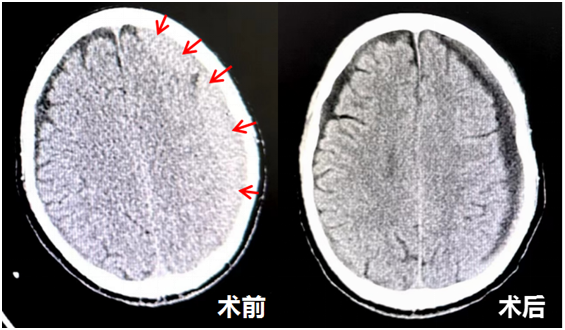

此名老年患者2月前不慎摔伤头部,近1月出现右侧肢体无力、言语不利症状,头颅CT检查发现左侧额颞顶枕部慢性硬膜下血肿,血肿广泛,脑组织受压明显,需手术治疗。针对慢性硬膜下血肿的常规治疗,神经外科的特色是局麻下微创穿刺引流手术,创伤极小,对患者影响甚微。但对于穿刺部位的选择,常规方法是根据影像资料凭借经验选择穿刺位点,但容易出现穿刺位点不够理想,影响血肿的有效引流。

本着精益求精的态度,神经外科副主任医师应建有利用神经导航定位系统,把患者术前的影像学资料与血肿的具体位置通过高性能计算机紧密地结合起来,进行导航术前规划,直观地显示了硬膜下血肿的三维空间位置,精准地设计出手术穿刺位点,科学地指导微创穿刺引流手术,大大提高了手术的精准性和成功率。本次神经导航引导下慢性硬膜下血肿局麻微创穿刺手术的顺利完成,体现了现代神经外科微创精准、快速康复的精髓。